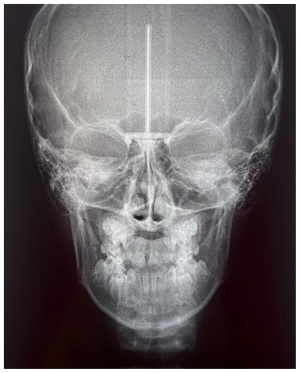

The patient was a young female presenting with a Class III dento-skeletal malocclusion, which was treated using the AMCOP® TC appliance. A comprehensive diagnostic protocol was carried out both before and after treatment, including orthopantomography (Figure 2–3), postero-anterior teleradiography (Figures 4, 5), latero-lateral cephalometric radiography (Figures 6, 7), cephalometric analysis (Tables 1, 2), as well as extraoral (Figures 8, 9) and intraoral photographs (Figures 10, 11). The extraoral examination revealed an edge-to-edge incisal relationship and the presence of a midline diastema. Pre-treatment cephalometric analysis (Deltadent® Lana, Bolzano, Italy) confirmed the diagnosis of a skeletal Class III malocclusion. The treatment plan involved the use of the AMCOP® TC appliance. The patient was instructed to wear the device for two hours in the afternoon and throughout the night for the first six months, followed by nighttime use only for an additional six months. Upon completion of the treatment, the patient achieved a Class I occlusion, with correction of both overjet and overbite. Additionally, the device facilitated tongue re-education and contributed to the postural realignment of the first cervical vertebra.